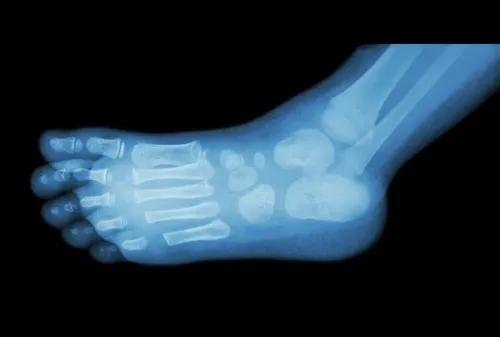

Para diagnosticar un espolón, los médicos suelen utilizar una radiografía común. No obstante, a simple vista también se pueden ver, ya que son unas pequeñas protuberancias causadas por la acumulación de calcio, como se ha mencionado antes.